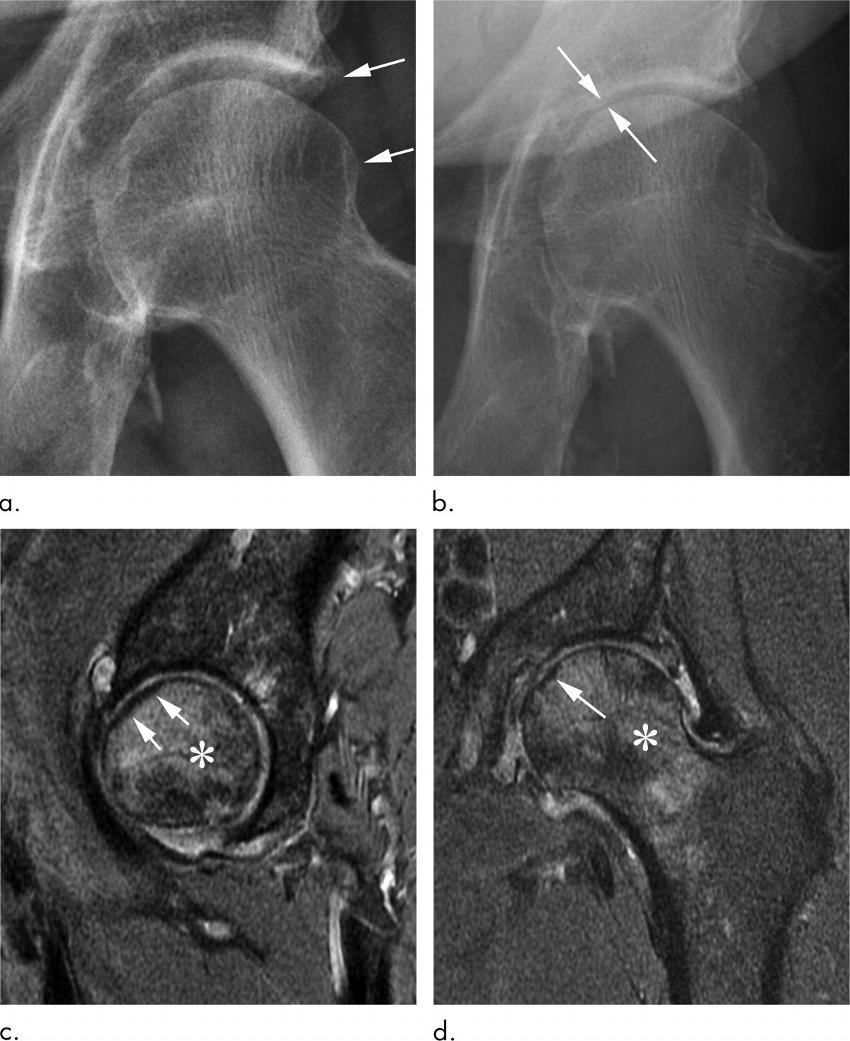

Figure 4. Osteonecrosis in a 29-year-old man who presented with right hip pain. (a) Anteroposterior radiograph of the pelvis shows osteonecrosis in the right femoral head, with preserved femoral head contours (arrows). He subsequently went to the sports medicine clinic and received a right hip joint corticosteroid injection for pain. (b) Three months later, he was referred to our institution for repeat intra-articular corticosteroid injection. The patient presented with a severe limp when walking and described the pain as worse than his original pain. Preprocedural sagittal US image shows a defect in the anterior right femoral head cortex (black arrow) and moderate joint effusion with a severely thickened anterior joint capsule (white arrows). The intra-articular corticosteroid injection was cancelled given the US findings, and the referring orthopedic physician was informed of the findings. (c) Repeat anteroposterior right hip radiograph obtained 1 week after US when the patient was seen in the orthopedic clinic for a follow-up visit enabled confirmation that the superior femoral head articular surface had collapsed (arrows), and the patient underwent right hip joint replacement.